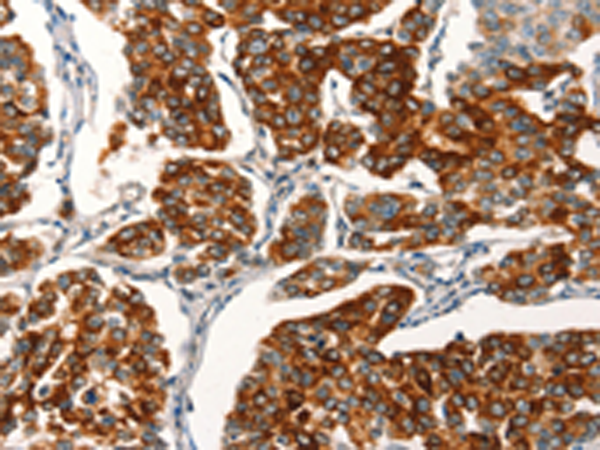

分类: 科研抗体货号: P04628别名: EHK3; EK11; EHK-3; HEK11应用: IHC反应种属: Human, Mouse, Rat